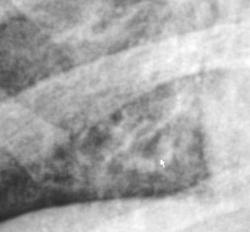

На рентгенограмме органов грудной полости (иллюстрация 1) справа в средних и нижних отделах легочного поля определяется усиление и обогащение легочного рисунка, имеет место усиление и обогащение тени правого корня в области хвоста. Медио-базально справа определяются ячеистые структуры.